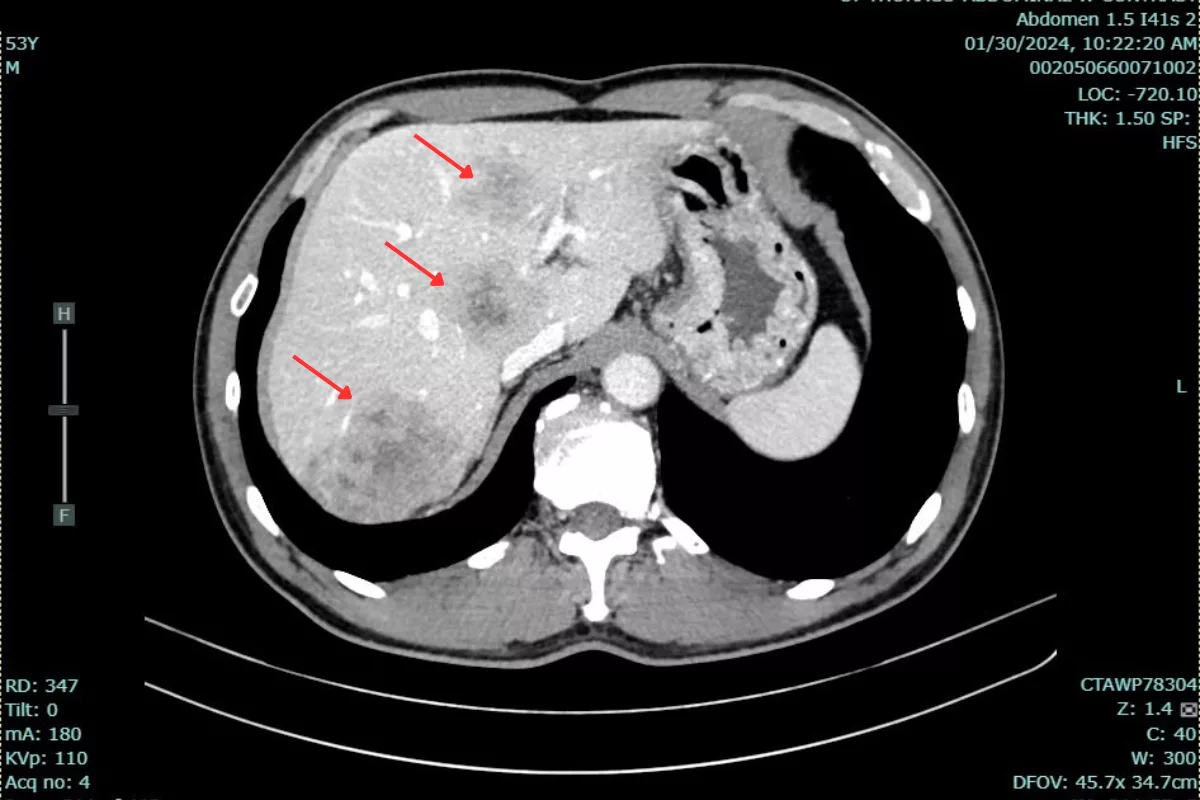

The cancer was first detected during a routine health check-up over a year ago. At that time, the patient had a large tumor located 5 cm from the anal margin, thickening of the rectal wall, and about 15 metastatic tumors in the liver, with the largest measuring 48x83x50 mm. The patient’s CEA tumor marker level was 105.6 ng/mL, significantly exceeding the normal threshold of under 5 ng/ml.

Dr. Bui Quang Loc reported:”The patient responded well to treatment. After the first cycle, some of the smaller liver lesions were no longer visible on post-treatment CT scans. After nearly a year, the largest liver lesion’s volume decreased from 78 mL to 27.26 ml. Liver metastases remained stable after treatment. Additionally, the patient’s CEA level dropped from 105.6 ng/ml to 33.6 ng/ml.”This patient’s treatment journey is a strong testament to the effectiveness of a personalized, multimodal approach in managing metastatic rectal cancer. The dedicated monitoring, tailored regimen adjustments, and close patient follow-up by the medical team at Hanoi French Hospital played a crucial role in not only controlling the disease but also improving the patient’s quality of life.